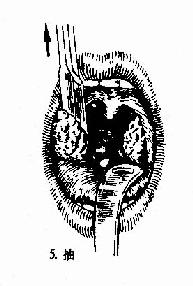

(二)挤切法(guillotine method)(图6-3):

2.操作:病人取仰卧或坐位,助手将其头部固定,置入开口器后,手术者以压舌板压舌,暴露扁桃体下极,右手持挤切刀,从扁桃体下极套入,再转动刀环,使其位于扁桃体和咽腭弓之间,将扁桃体后面及上极套入,并向舌腭弓方向提起,这时扁桃体在舌腭弓下隆起成一“包块”,即用左手拇指或食指将“包块”挤压入环内,随即收紧刀柄,推动刀杆前进,使刀片切入刀环的尽端,以迅速有力的扭转及提拔动作切下扁桃体。以同法切除对侧扁桃体。助手迅速将患者头部侧转,使其将血吐出。止血方法同剥离法。

图6-3 扁桃体挤切术